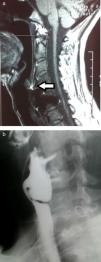

Cervical computed tomography (CT) and magnetic resonance imaging (MRI) (Fig. 1A) showed detachment and migration of the arthrodesis plate, which was in contact with the posterior oesophageal wall. Barium oesophagogram (EGD) revealed a protrusion of the metallic plate on a pharyngo-oesophageal saccular formation measuring 3–4cm (Fig. 1B). The study was completed with upper gastrointestinal (UGI) endoscopy, where the osteosynthetic piece was seen to be completely included in the posterior wall of a large pharyngo-oesophageal diverticulum. With these findings, we decided to surgically treat the patient with left cervicotomy, observing a wide-based pharyngo-oesophageal diverticulum in whose posterior wall the metallic arthrodesis plate was entirely included. This was dissected and followed by cricopharyngeal myotomy with reinforcement sutures. The diverticulum and plate were completely removed after the fixation screws had been withdrawn (Fig. 2A and B). Last of all, bone stability was analysed. The study of the surgical specimen showed a sac formation measuring 3.5cm×2.5cm with congestive mucous and histology compatible with Zenker diverticulum. The patient had an uneventful recovery and was discharged on the 10th day post-op after radiologic confirmation of proper passage of contrast and no signs of leakage.

Fig. 1.

Preoperative images: (a) sagittal view of cervical MRI showing the arthrodesis plate in close contact with the posterior oesophageal wall (arrow); (b) oesophagogram with barium contrast showing the imprint left by the metal prosthesis with screws over a cervical oesophageal sac formation.